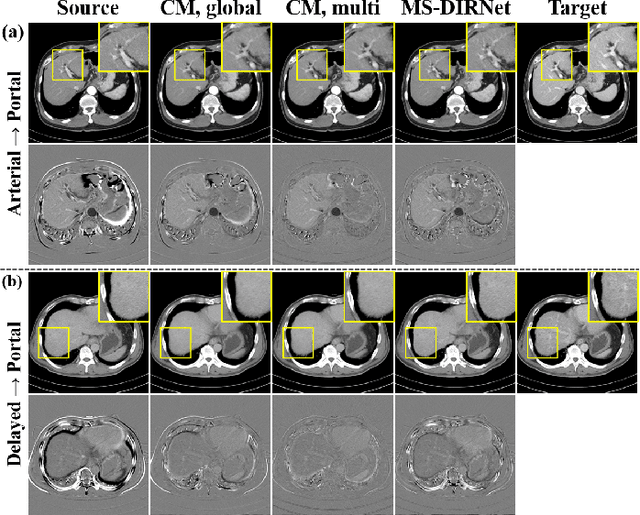

Abstract:Image registration is a fundamental task in medical image analysis. Recently, deep learning based image registration methods have been extensively investigated due to their excellent performance despite the ultra-fast computational time. However, the existing deep learning methods still have limitation in the preservation of original topology during the deformation with registration vector fields. To address this issues, here we present a cycle-consistent deformable image registration. The cycle consistency enhances image registration performance by providing an implicit regularization to preserve topology during the deformation. The proposed method is so flexible that can be applied for both 2D and 3D registration problems for various applications, and can be easily extended to multi-scale implementation to deal with the memory issues in large volume registration. Experimental results on various datasets from medical and non-medical applications demonstrate that the proposed method provides effective and accurate registration on diverse image pairs within a few seconds. Qualitative and quantitative evaluations on deformation fields also verify the effectiveness of the cycle consistency of the proposed method.

Abstract:Medical image registration is one of the key processing steps for biomedical image analysis such as cancer diagnosis. Recently, deep learning based supervised and unsupervised image registration methods have been extensively studied due to its excellent performance in spite of ultra-fast computational time compared to the classical approaches. In this paper, we present a novel unsupervised medical image registration method that trains deep neural network for deformable registration of 3D volumes using a cycle-consistency. Thanks to the cycle consistency, the proposed deep neural networks can take diverse pair of image data with severe deformation for accurate registration. Experimental results using multiphase liver CT images demonstrate that our method provides very precise 3D image registration within a few seconds, resulting in more accurate cancer size estimation.